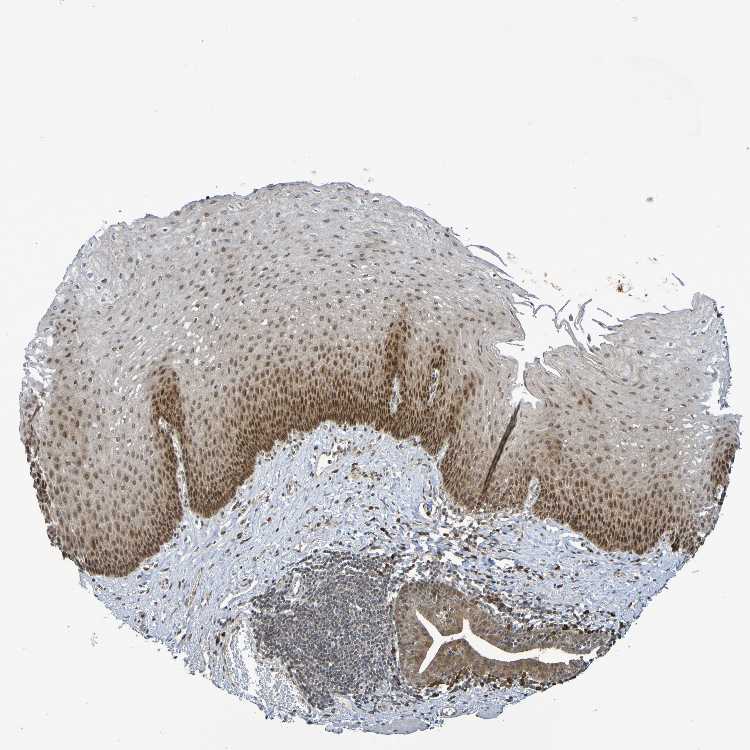

ESOPHAGUS - Antibody stainingi

Antibody staining in the annotated cell types in the current human tissue is reported as not detected, low, medium, or high, based on conventional immunohistochemistry profiling in selected tissues. This score is based on the combination of the staining intensity and fraction of stained cells.

Each image is clickable and will lead to virtual microscopy that enables deeper exploration of all samples and also displays staining intensity scores, fraction scores and subcellular localization as well as patient and tissue information for each sample.

Antibody HPA063275Antibody HPA067326Antibody CAB012652

Squamous epithelial cells Not detectedNot detectedMedium